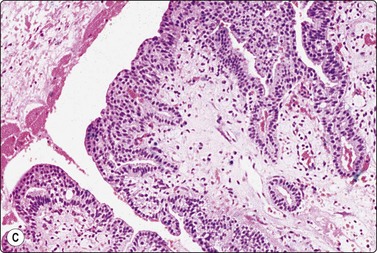

Spiradenoma is closely related to and resembles cylindroma. Smears are highly cellular, of clustered, variably cohesive small basaloid epithelial cells with uniform oval dark nuclei and a homogeneous chromatin. A more or less obvious acinar/tubular arrangement of the cells is discernible, but a dual population of small dark and larger pale epithelial cells as seen in histological sections is difficult to appreciate in smears. Globules of hyaline stromal material are characteristic but were scant in the case illustrated here (Fig. 14.8). The main differential diagnosis is adenoid cystic carcinoma.29

image image

Fig. 14.8 Eccrine spiradenoma

(A) Clustered and dissociated small basaloid cells with relatively uniform dark nuclei; suggestion of acinar/tubular grouping; minimal amount of hyaline stroma (MGG, IP); (B) Corresponding tissue section (H&E, IP).